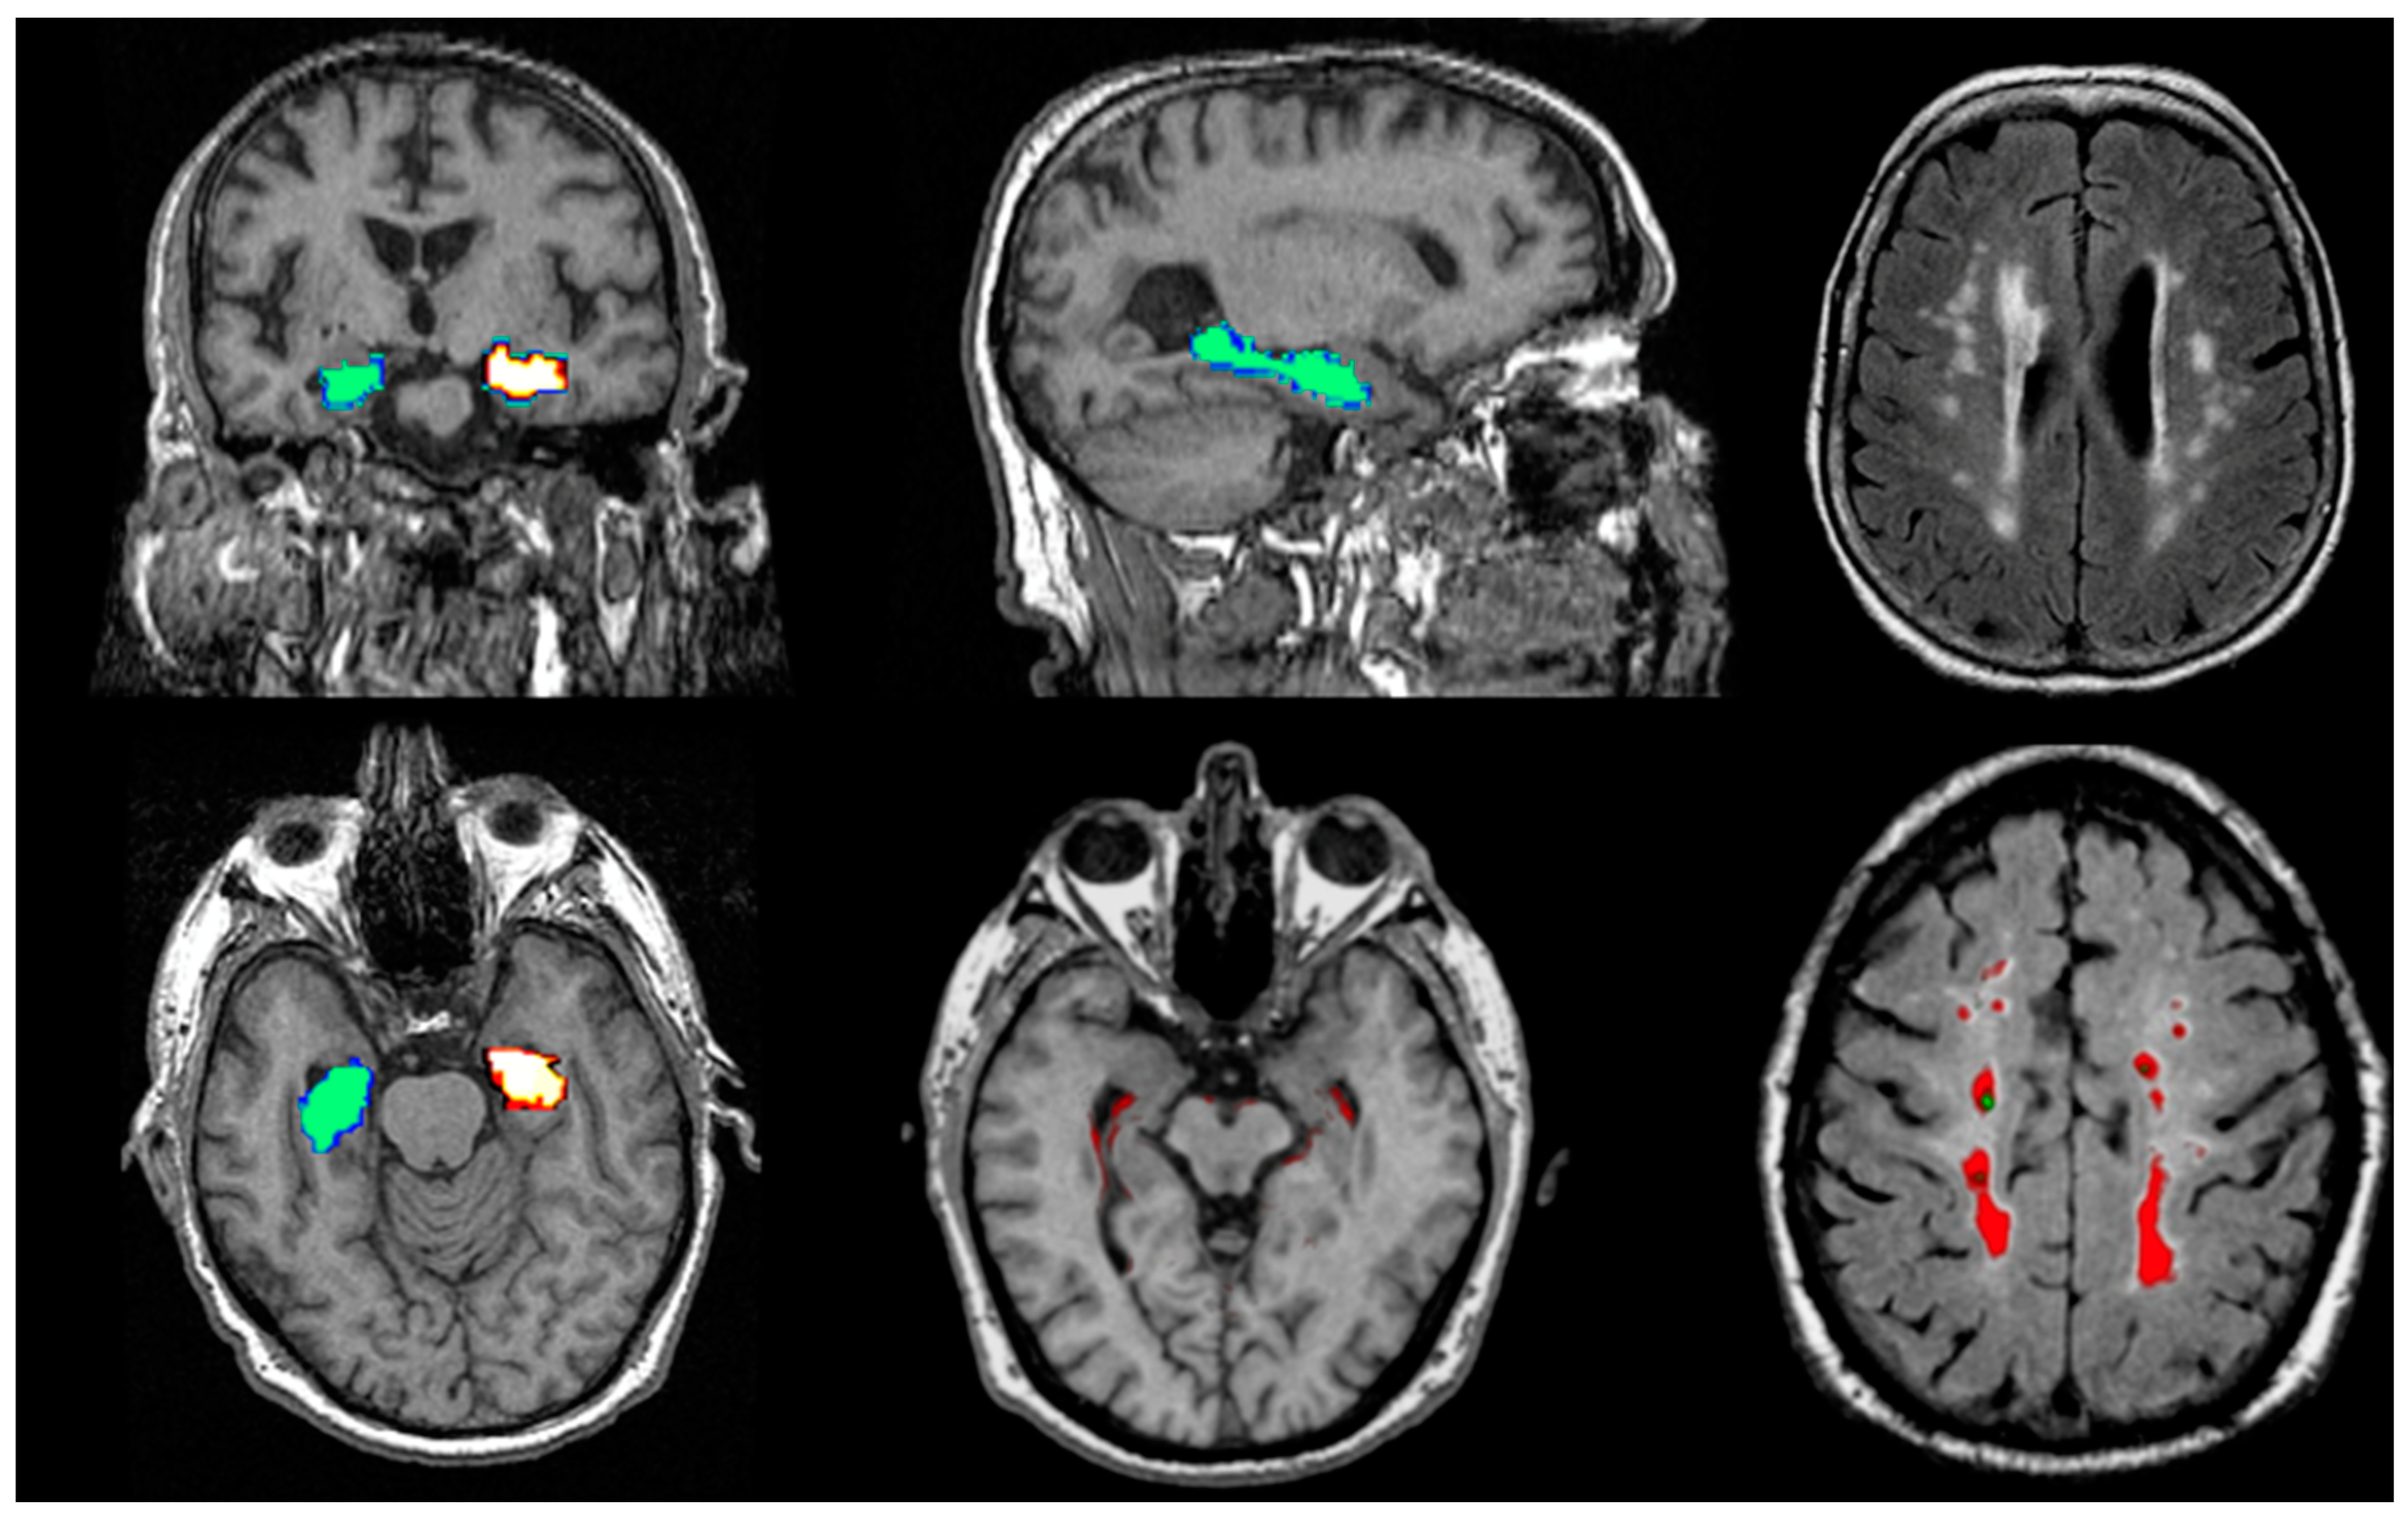

Amyloid PET

Tau PET

Structural Biomarkers

MRI Biomarkers in AD